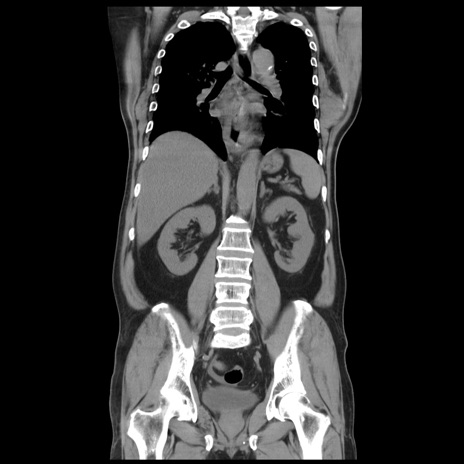

症例20(冠状断像)

【症例】 60歳代男性

【主訴】 腹部膨満、嘔吐

【現病歴】5日前頃より倦怠感を認め食事量減少し4日前の朝嘔吐、食事摂取困難となった。 3日前近医受診し点滴施行され整腸剤などを処方された。 当日他院を受診し、腹部膨満著明、炎症反応の上昇(CRP10.8、WBC11200)あり、紹介受診となる。

【身体所見】 意識JCS1 受け答えがはっきりしないBP 111/57mHg、 P 67bpm、、BT35.2°C、SpO2 97%(RA)、 腹部:膨隆、打診で鼓音あり、全体的に圧痛有り、腸蠕動音(-)、反跳痛ははっきりせず。

【データ】WBC 11400、CRP 14.20